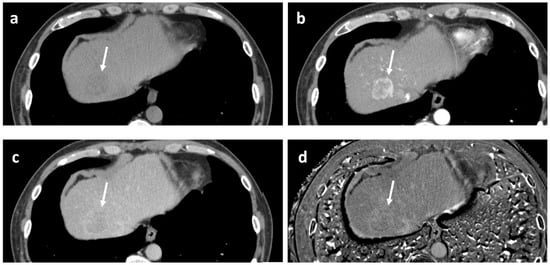

As for the scanning protocol parameters, in all papers cited here [19,26,27,28], PVP was obtained 30 s after AP delay time; therefore, there was considered to be little concern about the bias originating from technical aspects when interpreting their data. Representative cases are illustrated in Figure 4.

Figure 4. Dynamic gadoxetate-enhanced MRI in two representative cases ((a,b) and (c,d)). Both lesions exhibit arterial phase hyperenhancement (a,c), but in the former, there is no portal phase washout ((b) arrows), whereas in the latter, there is apparent portal phase washout ((d) arrow); the former pathologically turned out to be well to moderately differentiated hepatocellular carcinoma (HCC), and the latter to be poorly differentiated HCC.